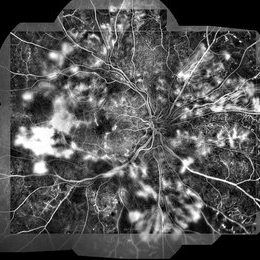

Syphilis Neuroretinopathy

Female patient, 21-years-old, with complaint of low vision in the right eye for 3 years. According to information from the patient's history, at the time she noticed the low vision, it also coincided with a picture of a strong urinary infection as well as episodes of constant tonsillitis. Yes, the patient did not seek medical attention and self-medicated with antibiotics. In ophthalmologic evaluation, as well as examinations of color retinography and ocular fundus autofluorescence, important pigmentary alterations were observed following vascular arches with pigment mobilization in osteoclasts (aspect of a unilateral pigmentary retinitis secondary to the inflammatory process). Which suggested inflammatory process sequelae. Through the laboratory tests, he had positive (+) confirmation for SYPHILIS NEURORETINOPATHY .

Photographer: JEFFERSON R SOUSA - Study Center and Ophthalmological Research Dr. Andre M V Gomes, Institute Dr. Suel Abujamra São Paulo-Brazil

Imaging device: Fundus camera Topcon TRC-50 DX, Imaginet 5.0, angle de 50 graus. Flash 100 / Mosaic with 10 images.

Condition/keywords: autofluorescence imaging, neurosyphilitic optic atrophy, retinitis pigmentosa, syphilis, syphilis neuroretinopathy